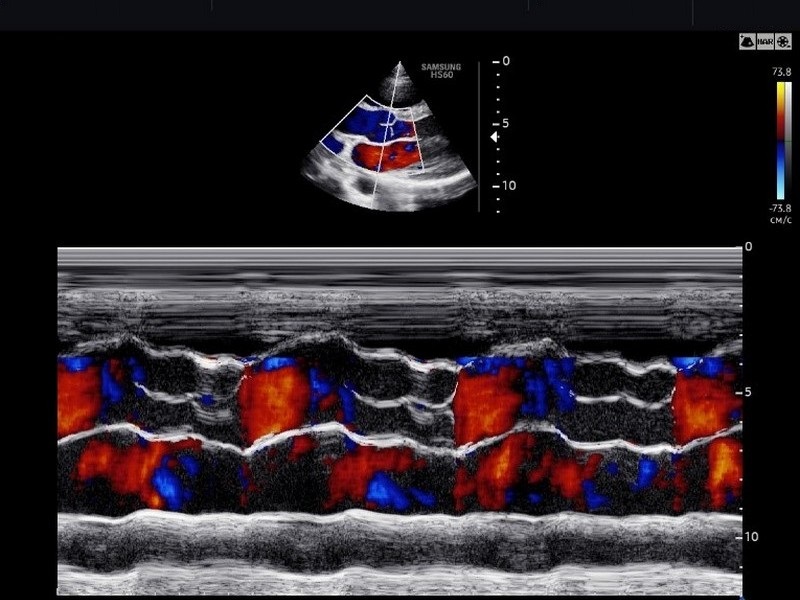

Метод основан на способности ультразвука отражаться от структур сердца, имеющих разную плотность. Современная эхокардиография — это мультипараметрическое исследование. Оно включает в себя не только визуализацию в В-режиме (серая шкала), но и обязательное использование допплерографических методик (цветное, импульсно-волновое, непрерывно-волновое картирование) для оценки внутрисердечной гемодинамики. Сегодня ЭхоКГ позволяет неинвазивно и с высокой точностью выявить патологию на ранних стадиях, когда клинические симптомы могут еще отсутствовать.

В РНПЦ исследование проводится на аппаратах экспертного класса (например, GE Logiq, Esaote MyLab или аналогичных), оснащенных специализированными кардиологическими датчиками и пакетами программ для углубленного анализа. Аппаратура позволяет проводить исследование в стандартных режимах (М-режим, 2D-режим) и всех режимах допплера (спектральный, цветовой, тканевой).

Процедура безопасна и безболезненна. Пациент раздевается до пояса и ложится на кушетку, обычно на левый бок. Врач устанавливает датчик в различных точках грудной клетки. Производятся измерения размеров предсердий и желудочков, толщины стенок, и скорости потоков крови, расчет фракции выброса. Исследование может выполняться как самостоятельная процедура, так и в комплексе кардиологического обследования.